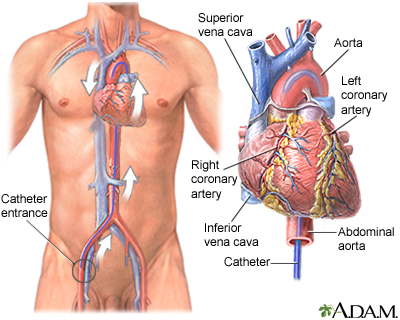

- Sometimes the PDA can be closed with a procedure that does not involve surgery. The procedure is most often done in a laboratory that uses x-rays. In this procedure, the interventional cardiologist makes a small cut in the groin. A wire and tube called a catheter is inserted into an artery in the leg and passed up to the heart. Then, a small metal coil or another device is passed through the catheter into the infant's ductus arteriosus artery. The coil or other device blocks the blood flow, and this corrects the problem.

- A newer method does not require surgery. An interventional cardiologist places a small wire through an artery in the groin and up to the aorta. A small balloon is then opened up in the narrow area of the aorta. A stent or small tube is left there to help keep the aorta open. The procedure is done in a laboratory with x-rays. This procedure is often used when the coarctation reoccurs after it has been fixed.

- Sometimes, an ASD can be closed without open-heart surgery. First, the interventional cardiologist makes a tiny cut in the groin. Then they insert a wire into a blood vessel that goes to the heart. Next, two small umbrella-shaped "clamshell" devices are placed on the right and left sides of the septum. These two devices are attached to each other. This closes the hole in the heart. Not all medical centers do this procedure.

- Some septal defects can be closed without surgery. The procedure involves passing a small wire into the heart and placing a small device to close the defect.